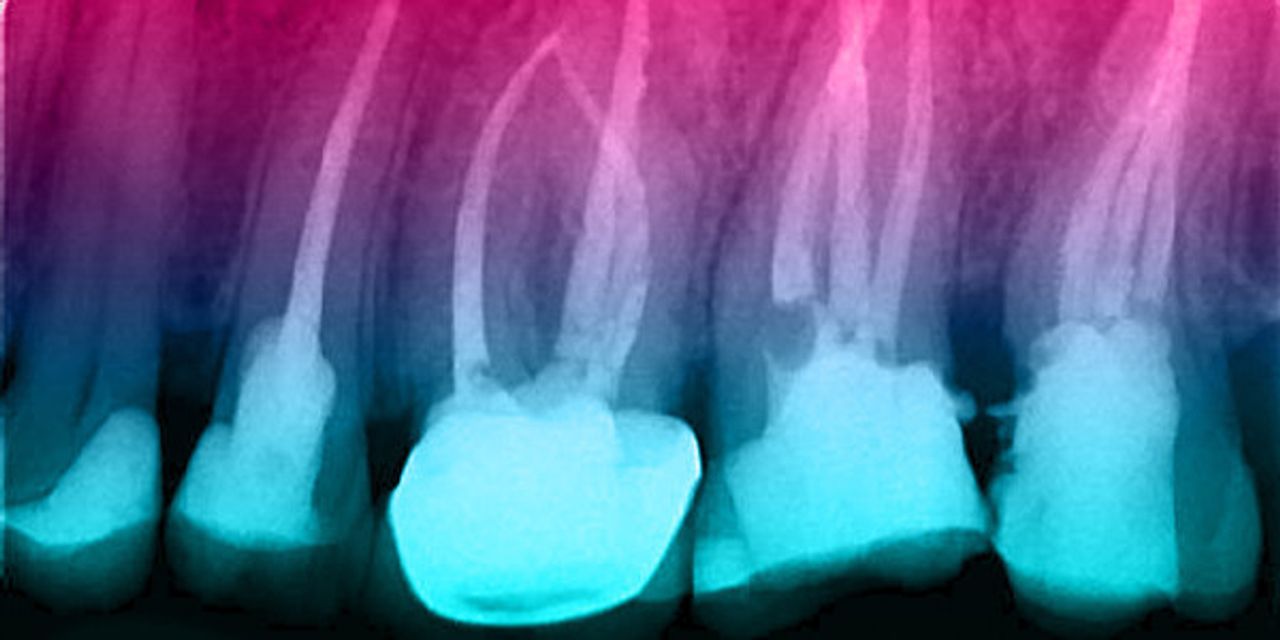

Значительные успехи произошли в эндохирургии за последние годы. Микроскоп уже вошёл в повседневное применение, а также разработаны ультразвуковые наконечники. Эти наконечники радикально изменили наш подход и теперь мы можем проводить процедуры, схожие с традиционной эндодонтией. С помощью данного метода теперь можно сохранить многие зубы, которые обычно заменялись имплантами. В этой презентации будет рассмотрена актуальная литература, описывающая результаты эндохирургии в сравнении с традиционным перелечиванием, а также будет рассмотрено применение новых ультразвуковых инструментов.